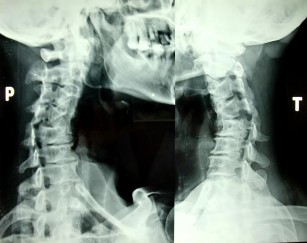

- X-quang là phương tiện phổ biến, cần thiết và hữu dụng. Là phương tiện chẩn đoán chính xác, rẻ tiền, nhanh chóng. Chụp X-quang thường qui gồm hình thẳng, nghiêng, chéo ¾ P và ¾ T. Nếu các X-quang không thấy tổn thương xương

mà phần mềm phía trước CSC sưng, ta nghĩ đến tổn thương D/C dọc trước. Trường hợp này nên làm nghiệm pháp kéo giãn rồi chụp lại, đo độ hở bất thường của khoảng liên đốt [117]. Nếu X quang không thấy tổn thương mà lâm sàng có liệt tứ chi, chẩn đoán: chấn thương tủy sống cổ không thấy bất thường trên X-quang. Trong một số ít trường hợp phải nhờ tới X-quang cắt lớp điện toán để chẩn đoán. Chỉ định cộng hưởng từ hạt nhân khi có liệt và nghi ngờ có thoát vị đĩa đệm.

Hình 1.28: X- quang chéo 3/4P và 3/4T.